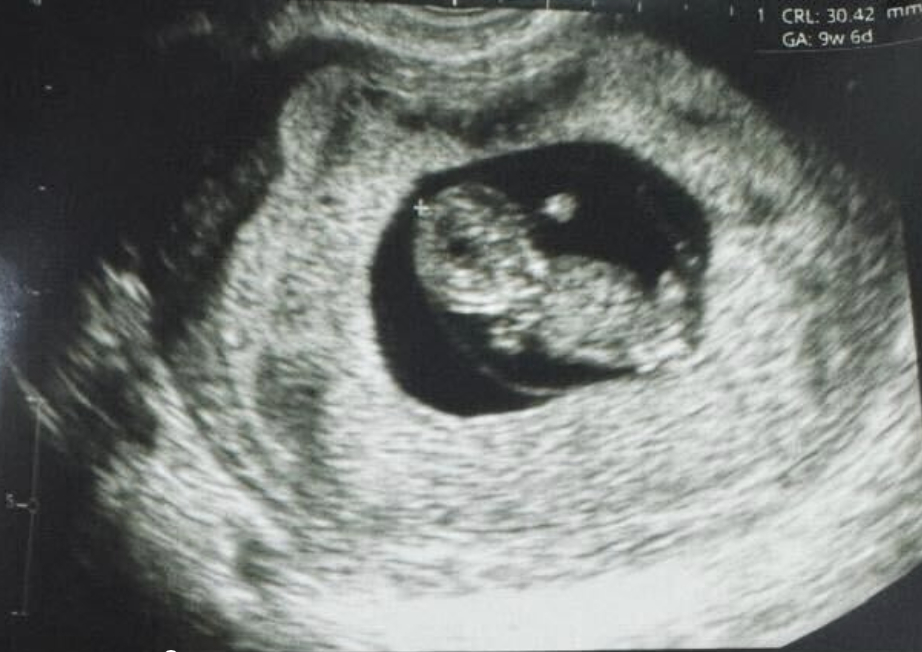

全球首例:使用誘導多能干細胞體外成熟卵子技術,成功產下一名嬰兒

紐約(?BUSINESS WIRE?)致力于推動女性健康治療方案發展的生物技術公司Gameto與2024年12月16日宣布,該公司利用 Fertilo 實現了全球首例活產。此次分娩在秘魯利馬的圣伊莎貝爾診所進行。